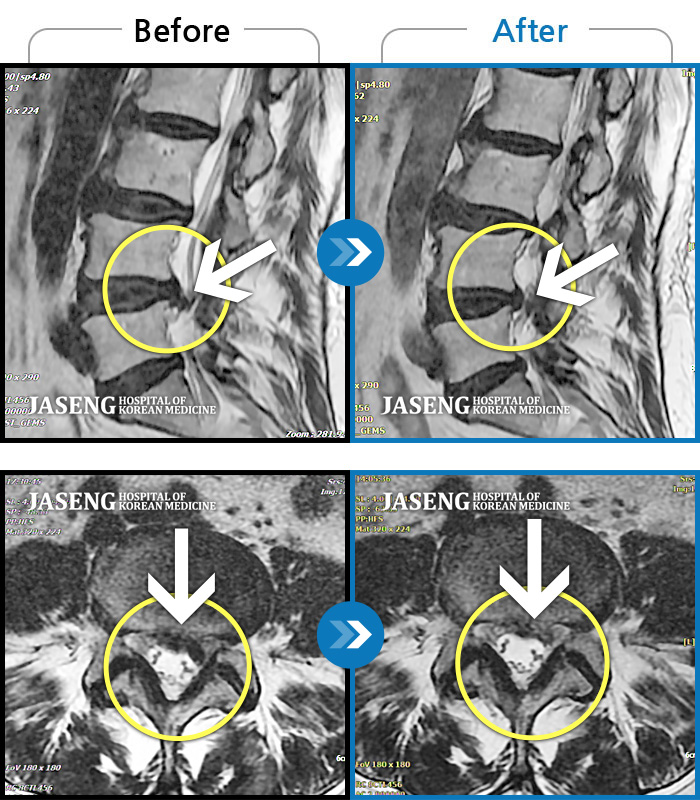

MRI 치료사례

좌측 허리와 골반에 통증, 좌측 다리에 통증과 저림